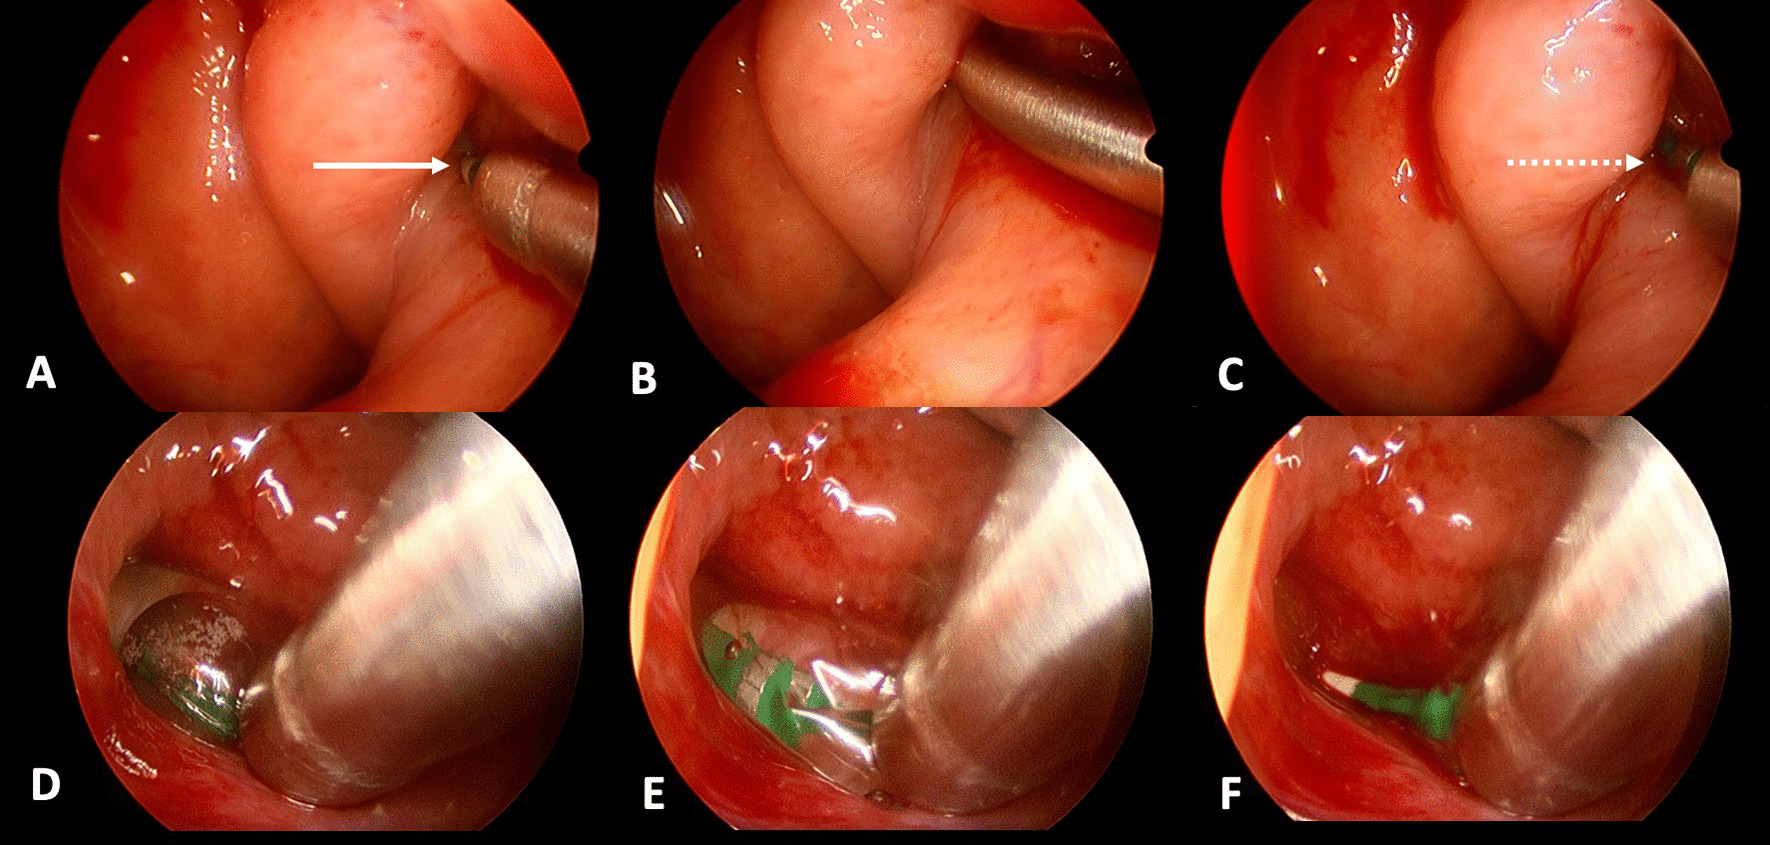

Fig. 3.

Eustachian tube orifice at the two week follow-up

In all twelve included patients, BDET with the EVB was carried out successfully. The endoscope was placed on the same side as the dilation device in all twelve cases. The malleable suction was used in 6 cases, the 45° device in 4 cases and the 70° in 1 case. In one single case the 45° device was used first, but since placement was not successful, the malleable device was subsequently used. Although the angle of the malleable device could theoretically be bent, it was left in its original position during the entire study period. Intraoperatively minor bleeding from the turbinate was noted in some cases, which was easily controlled with a transient packing of the nose with adrenalin- or xylometazoline-soaked patties. The nasal cavity was not packed postoperatively. No instances of major adverse events occurred. The mucosa was inspected in all twelve patients after dilation and no mucosal tears or abrasions were noted. The procedure time ranged between 15 and 20 min. Postoperative CT was carried out in all twelve cases on the day of surgery to assess for any damages. Special focus was given to the tissue of the eustachian tube and any obvious damages as well as the integrity of the carotid canal in comparison to the preoperative CT. Examples are shown in Fig. 4. None of the CT images showed carotid canal fracture or dehiscence, as well as gross tissue damage. All surgeries were performed in an ambulatory day surgery setting. None of the included individuals reported any adverse events during their time at home following surgery. After two weeks of follow-up, patients were asked about the occurrence of any adverse events. One patient suffered from temporary nasal obstruction for one to two days after the procedure, which was treated with nasal saline sprays. Transnasal endoscopy did not show any swelling at follow-up. No patient reported epistaxis, swelling of the face or emphysema. Pain was not mentioned as an issue by any of the included patients. The orifice of the eustachian tube was inspected at the two-week follow-up in all cases and showed unremarkable results (Fig. 3). There was no sign of infection, bleeding, blood clot, hematoma, infection, edema at the orifice folds, torus tobarius, and nasopharynx. The mean ETDQ-7 score before the surgery was 29.5 (range 7 – 41 points), as opposed to 16 (range 7–39 points) 2 months after dilation. Results of the individual ETDQ-7 questionnaires, tympanograms, average conductive hearing loss (average across 0.5, 1, 2 and 4 kHz) and pure tone audiogram (4-PTA—average across 0.5, 1, 2 and 4 kHz) can be found in Table 1.